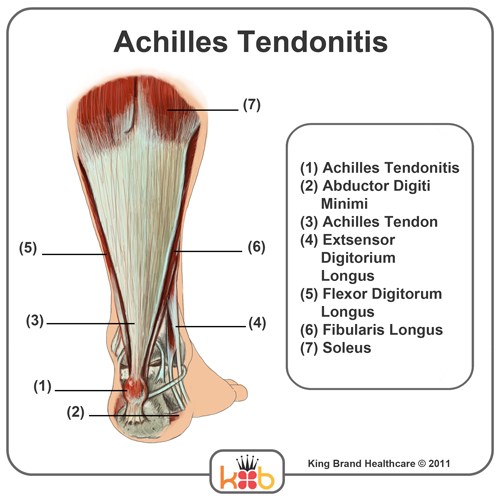

💥𝐀𝐜𝐡𝐢𝐥𝐥𝐞𝐬 𝐓𝐞𝐧𝐝𝐢𝐧𝐨𝐩𝐚𝐭𝐡𝐲💥 ——— 👣Achilles tendinopathy describes a …

Achilles Tendinopathy (Tendinitis and Tendinosis) – Complete Feet …

Achilles Tendinopathy | Mr Daniel Goldbloom | Melbourne

King Brand Ankle Images